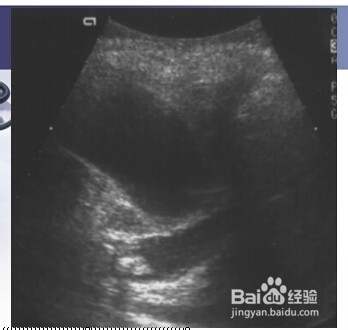

3、三:胆囊颈部结石。